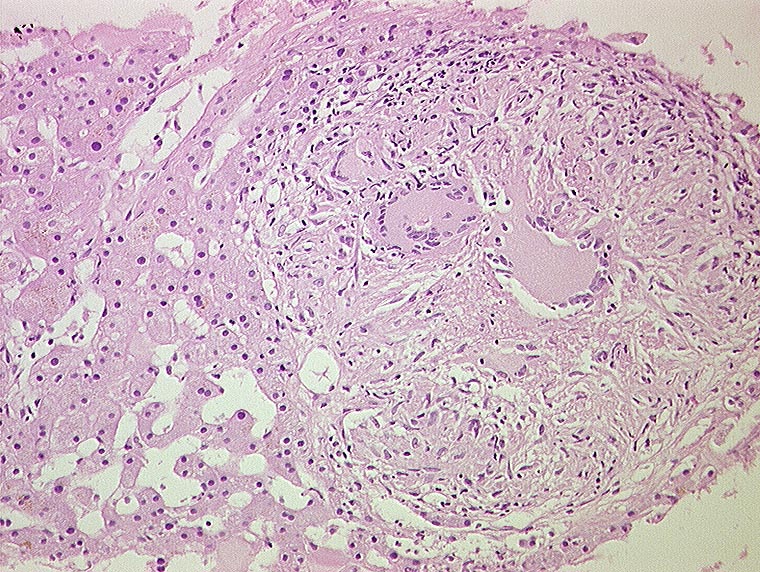

Miliartuberkulose der Leber

Entzündung infektiös

Leber, Gallenwege, Pankreas

Leber